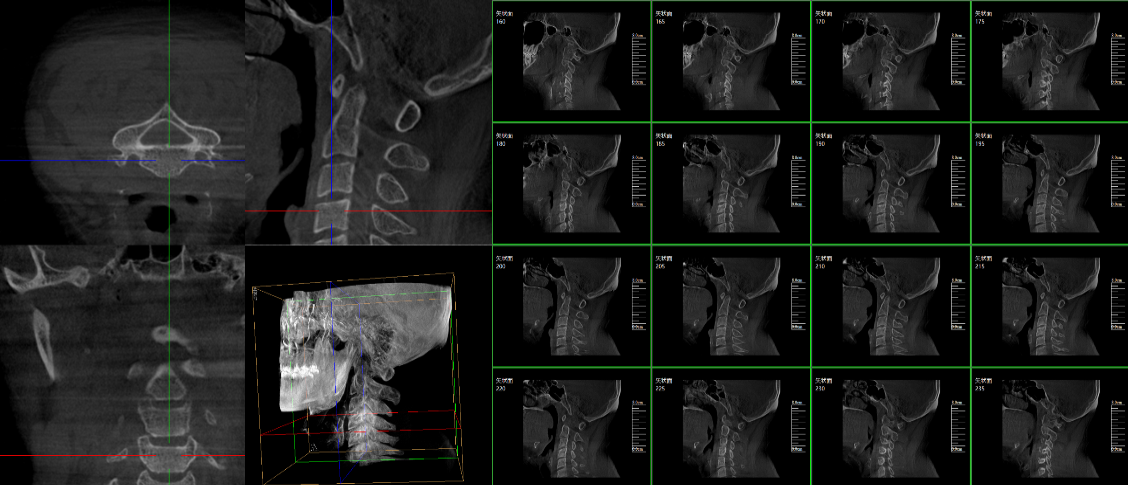

三維C臂,作為“術中CT”,能在術中快速地生成橫斷面、矢狀面、冠狀面和可旋轉的立體圖像,給術者提供360°無死角的觀察角度,全方位準確判斷骨組織和植入物的情況,為手術的實施提供保障,極大提高手術成功率,減少并發癥概率。主要適用于骨科、脊柱外科、矯形外科、創傷骨科及手術室等。

三維C形臂成像

普愛醫療三維C形臂具備術中實時三維成像,術中三維成像和橫斷面圖像提供多角度的手術診斷信息,輔助醫生進行術中評估判斷,諸如骨折復位情況和內植入螺釘的尺寸和位置,輔助手術更好地完成;三維成像視野大,提供更大的術中三維成像視野,采集更多圖像信息,可一次拍全全段頸椎、全段腰椎、七節胸椎、雙側骶骼關節、股骨頭及單側盆骨等。如果您想了解更多普愛三維C形臂優點及技術參數,歡迎咨詢我們。